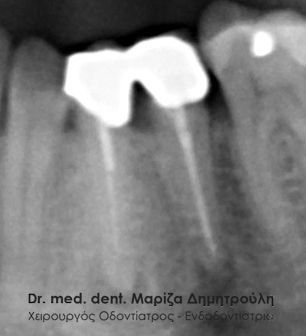

Root canal retreatment

BEFORE

AFTER